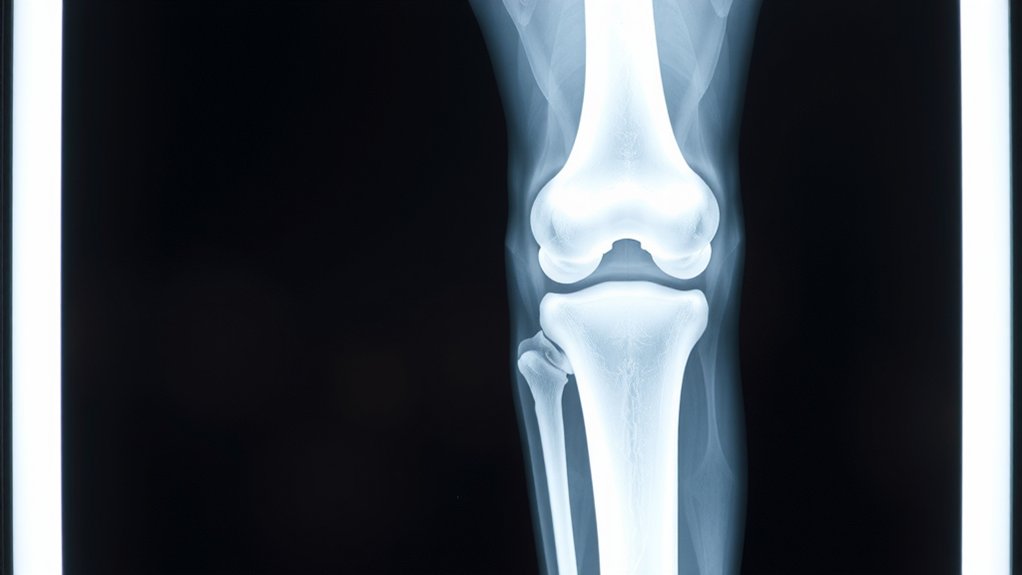

- On X‑ray: bright metal femoral cap and tibial tray; the plastic spacer looks dark; you may see screws and thin cement lines.

On the X-ray you’ll spot the metal femur cap, the tibial tray, maybe screws or cement lines, while the plastic spacer plays hide-and-seek because it’s mostly invisible. They should line up like soldiers—straight joint line, centered parts, patella tracking true—not crooked, not tilted, not “good enough.” See dark gaps, shifting edges, screw creep, or bone getting eaten away; that screams loosening and wear, and yes you call your surgeon now, not later.

Visible Components on Radiographs

X‑ray film doesn’t lie. You see the metal first: the bright femoral cap hugging the thighbone, the tibial baseplate like a shiny tray, maybe a stem plunging deeper. The plastic insert? It mostly disappears, a shadow gap that fools amateurs, not you. A round patellar button can glare back. Cement shows up as a pale cuff. Screws look like tiny drill bits daring you to blink. You want clarity, not guesswork, so you demand radiation safety and clean technique. Because blur isn’t mystery. It’s failure. Watch for image artifacts—buttons, zippers, motion streaks—that pretend to be problems. Don’t buy the illusion. Ask for sharp edges, balanced contrast, honest exposure, minimal noise. You paid for parts you can actually see, today. No excuses. Show the metal.

Alignment and Positioning Signs

You stared at metal; now you judge it. On the AP view, draw the hip‑knee‑ankle line. It should slice straight through the center of the femoral and tibial components. No lazy varus, no smug valgus. The tibial baseplate sits level to the joint line, with an even rim. On the lateral, you want controlled posterior slope, not a ski jump. Femoral component hugs the distal contour and stays parallel; the box isn’t tilted. Patella tracks midline, not sulking lateral. Pegs and keel look centered, not flirting with cortex. Rotation? Symmetric condylar shadows, equal overhang, clean trochlear groove. Compare limbs: gait symmetry starts here; stance width stops lying. If the metal lines up, you walk straighter. If it doesn’t, you feel it. Every single step.